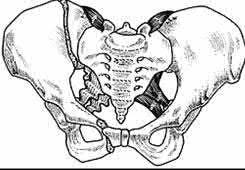

A 35 year-old female presents after prolonged extrication from a motor vehicle collision complaining of severe pelvic pain. Physical examination reveals diminished perianal sensation. She is otherwise neurologically intact. Figures A through D are radiographs and representative CT cuts of her injury. Which of the following nerve roots has likely been injured by the acute trauma?

The clinical scenario is consistent with a high-energy sacral fracture. The radiographs in figures A and B demonstrate a sacral fracture with posterior displacement of the right hemipelvis seen on the inlet view. Figures C and D are axial and sagittal CT images which show a displaced fracture of the right

hemisacrum along with a transvere fracture component through the S3 body . Diminished perianal sensation is concerning for an S2 nerve root injury.

Mehta et al reviewed the current management of sacral fractures. They note that the S1 and S2 nerve roots are more likely to be injured with sacral fractures as they occupy 1/3 to 1/4 of the neural foramina, as opposed to S3 and S4, which only occupy 1/6 of the neural foramina.

Robles reviewed the current literature to ascertain principles of evaluation and treatment for transverse sacral fractures. The author notes that injury to nerve roots S2 to S5 is manifested by impairment of urinary and anal continence and sexual function.

The first illustration demonstrates the sacral nerve root dermatomal distribution. The second shows a pelvic cadaver dissection demonstrating the sacral nerve roots as they exit the foramina.